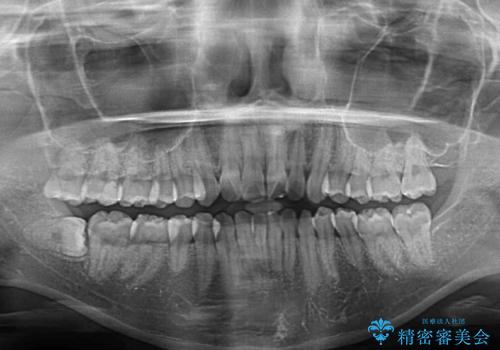

- 上下前歯のデコボコを気にして来院された患者様です。

インビザラインによる上下歯列の側方拡大と後方移動、IPR(歯と歯の間を削る)にるスペースの獲得により歯列を整えることとしました。

骨格的な左右差があったため、上下の正中を合わせることは困難かと思われましたが、何とか合わせることができました。

一方、骨格の差は改善できないため、奥歯の咬み合わせに物足りなさを感じました。